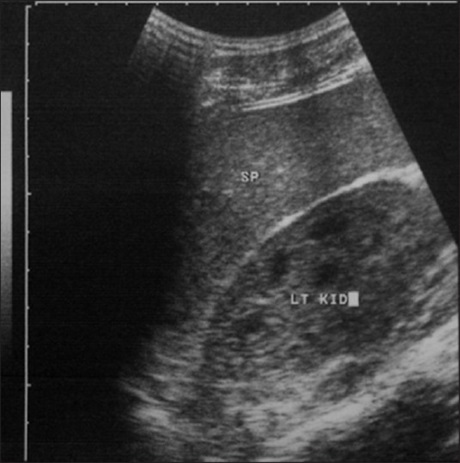

Renal Complications of sickle Cell Anemia in Zaria, Nigeria: An ultrasonographic Assessment

Dr. Philip Oluleke Ibinaiye, Aliyu Ahmadu Babadoko, Rasheed Yusuf, Abdul-Aziz Hassan (Author)

19-22

Views | PDF/EPUB Downloads : 258 / 28 / 22

DOI: https://doi.org/10.82235/wajr.vol20no1.220